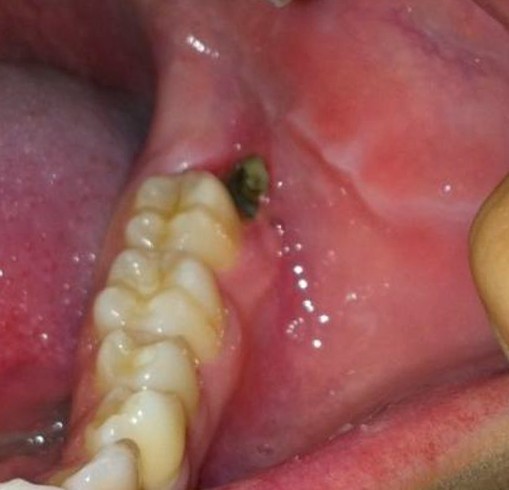

Có nên nhổ chân răng sâu hay không?

Câu hỏi: Thưa bác sỹ. Em có một chiếc răng hàm bị sâu đã rất lâu và hầu như phần thân răng đã mất và chỉ còn chân răng mà…